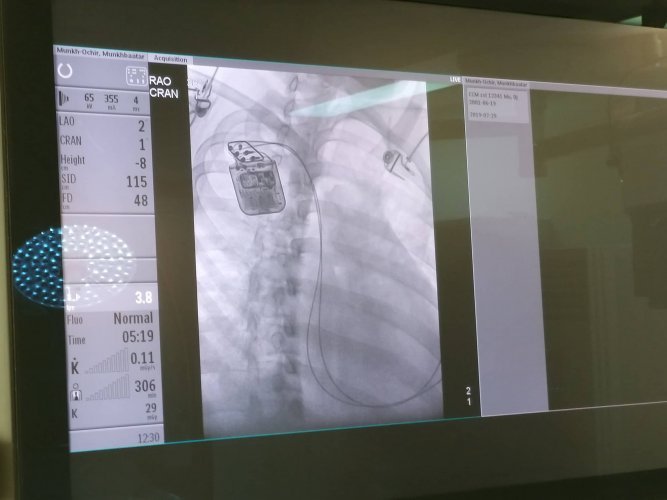

Улсын гуравдугаар эмнэлгийн Зүрхний хэм судлалын баг, Зүрхний дутагдлын баг, Эрчимт эмчилгээний нэгдсэн тасаг, Ангиографийн оношилгоо эмчилгээний хамтарсан баг зүрхний хүнд дутагдал бүхий 18 настай залуу эмчлүүлэгчид Зүрхний агшилтыг дэмжигч төхөөрөмж суулгах мэс засал эмчилгээг 07 сарын 29-ны өдөр амжилттай хийж гүйцэтгэлээ.

Эмчлүүлэгч М нь 18 настай бөгөөд зүрхний дутагдлын улмаас биеийн байдал туйлын тогтворгүй байсан ч багуудын хамтарсан эмчилгээний үр дүнд мэс засал эмчилгээг амжилттай хийсэн юм. Одоо эмчлүүлэгчийн биеийн байдлыг хянан эмийн эмчилгээг үргэлжлүүлж байна.